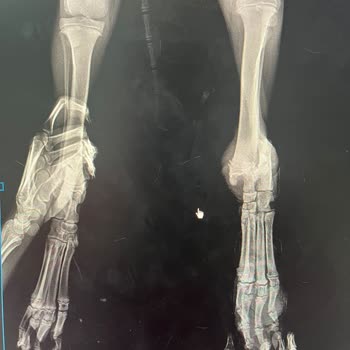

Yavru bir cana araç çarptı ve Axis Veteriner Kliniği'ne götürüldü. Ameliyat dediler, başka yolu yok, mecbur dediler. Ama maalesef hatalı, kusurlu ve yanlış bir ameliyat yaptılar. Şimdi de telefonu engellemişler. İlgisizlik ve ciddiyetsizlik var. Raporlar ve röntgenler hepsi mevcut.